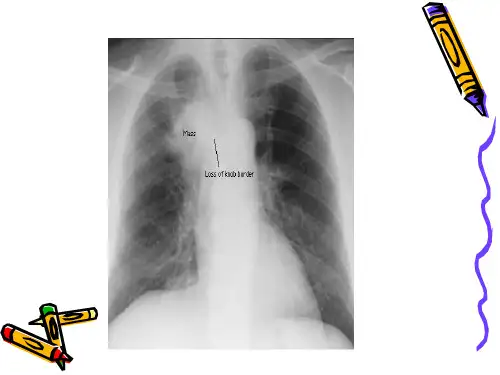

肺癌影像学检查X线检查方法及表现检查方法常规胸部X线片,包括正位和侧位,必要时加拍斜位或前弓位等。

表现中央型肺癌可见支气管阻塞征象,如肺不张、肺气肿等;周围型肺癌可见孤立性结节或肿块,常呈分叶状,边缘有细毛刺。